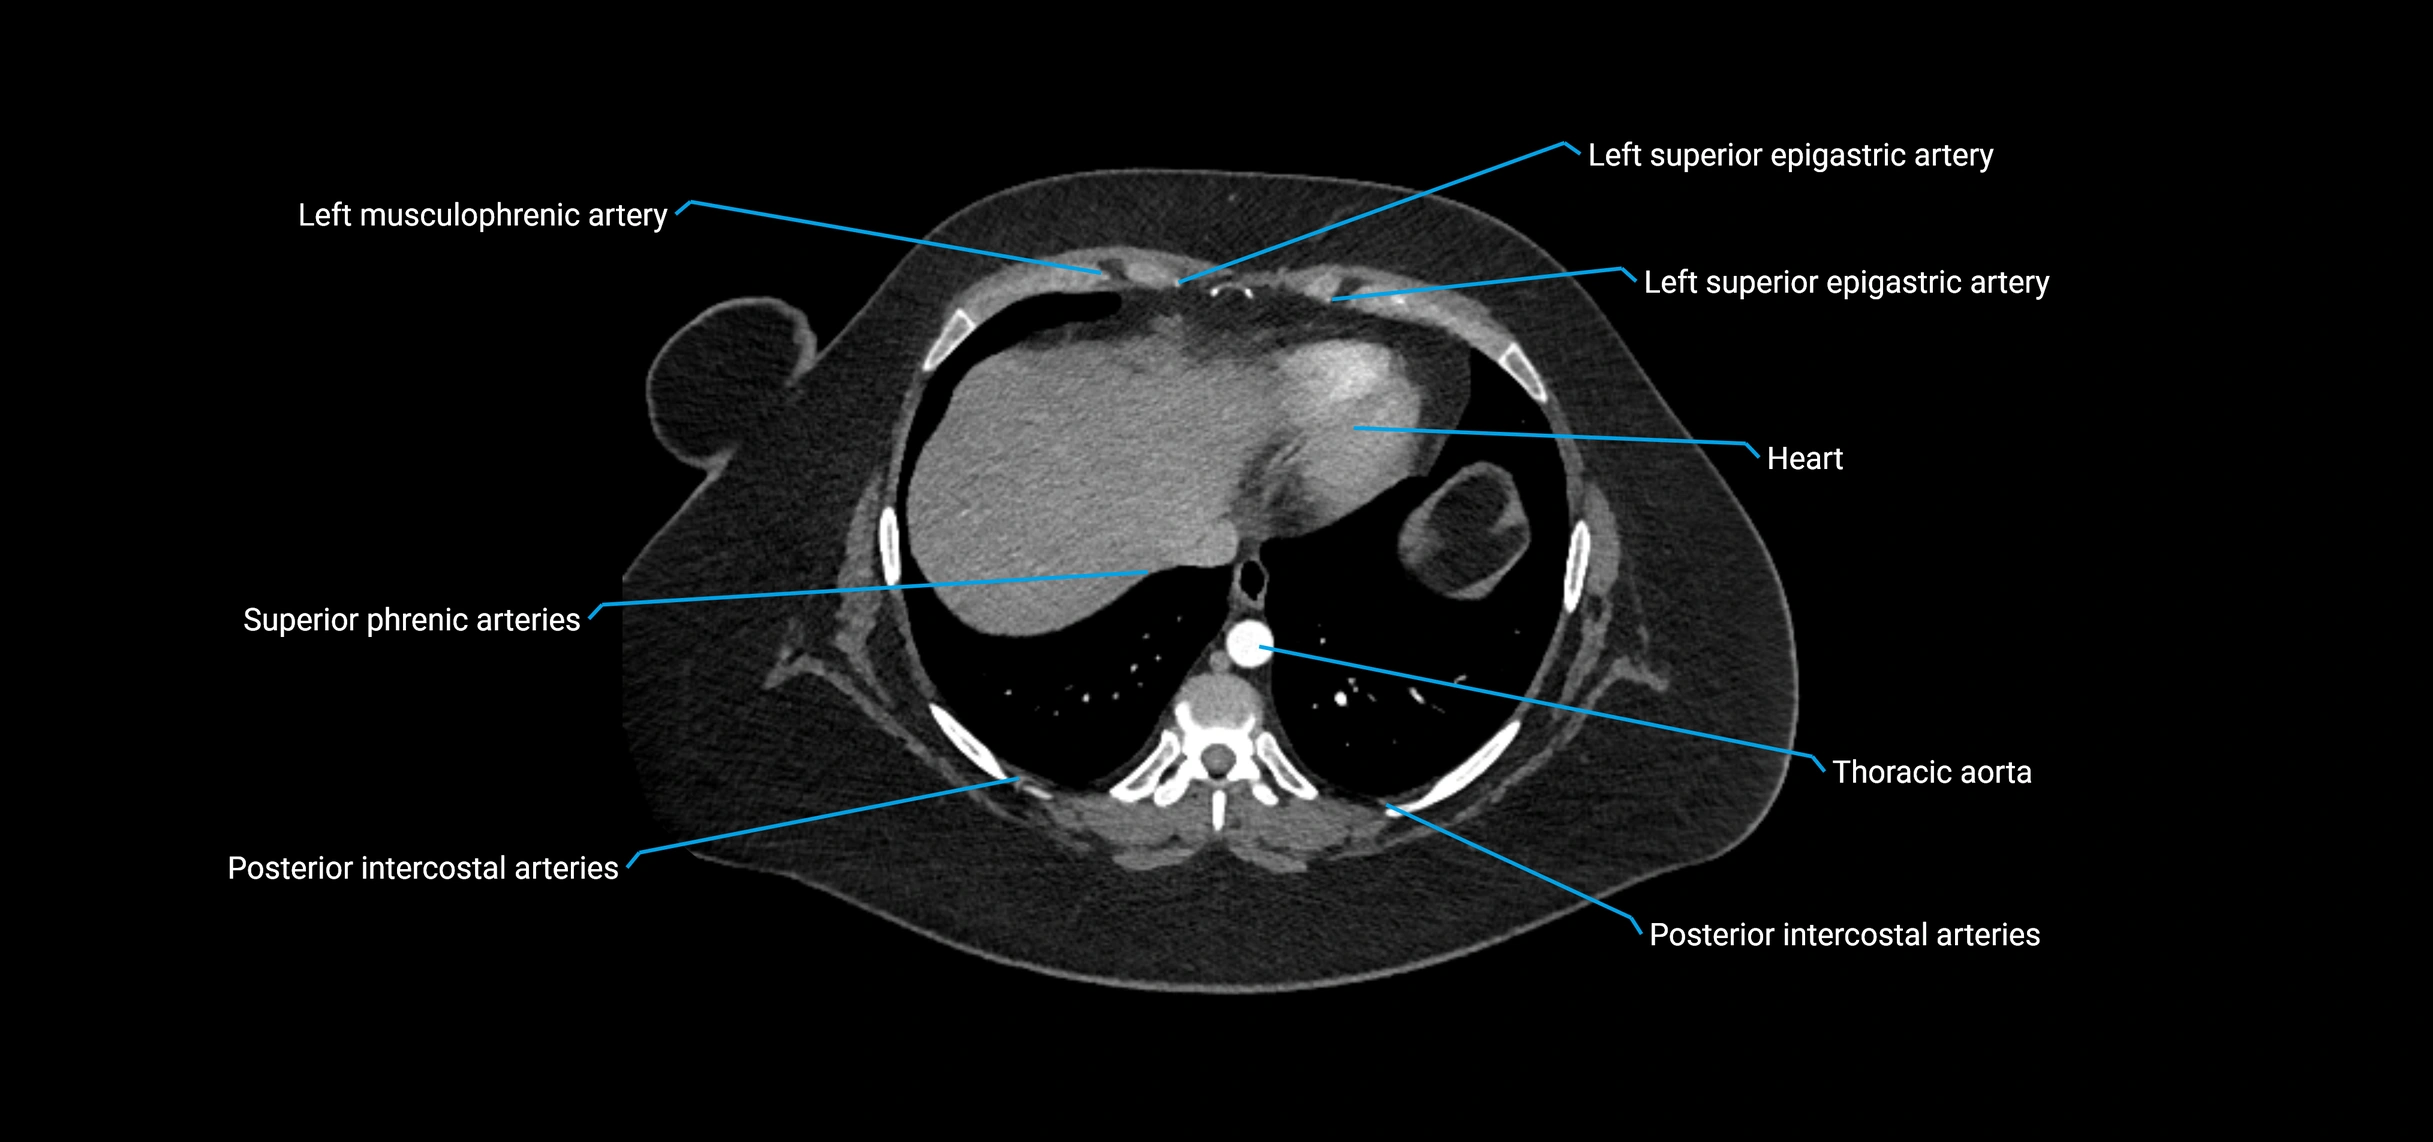

CT Appearance

Non-contrast CT:

• Appears as a tubular soft tissue structure anterior to vertebral bodies

• Calcified atherosclerotic plaques appear as hyperdense foci along the wall

• Useful for screening abdominal aortic aneurysm (AAA) size and mural calcification

Contrast-enhanced CT (CTA):

• Gold standard for abdominal aortic imaging

• Provides excellent detail of lumen, wall, aneurysm, thrombus, and branch vessels

• Multiplanar and 3D reconstructions help in aneurysm measurement, stent graft planning, and dissection evaluation

• Detects acute rupture, traumatic injury, or occlusion with high sensitivity